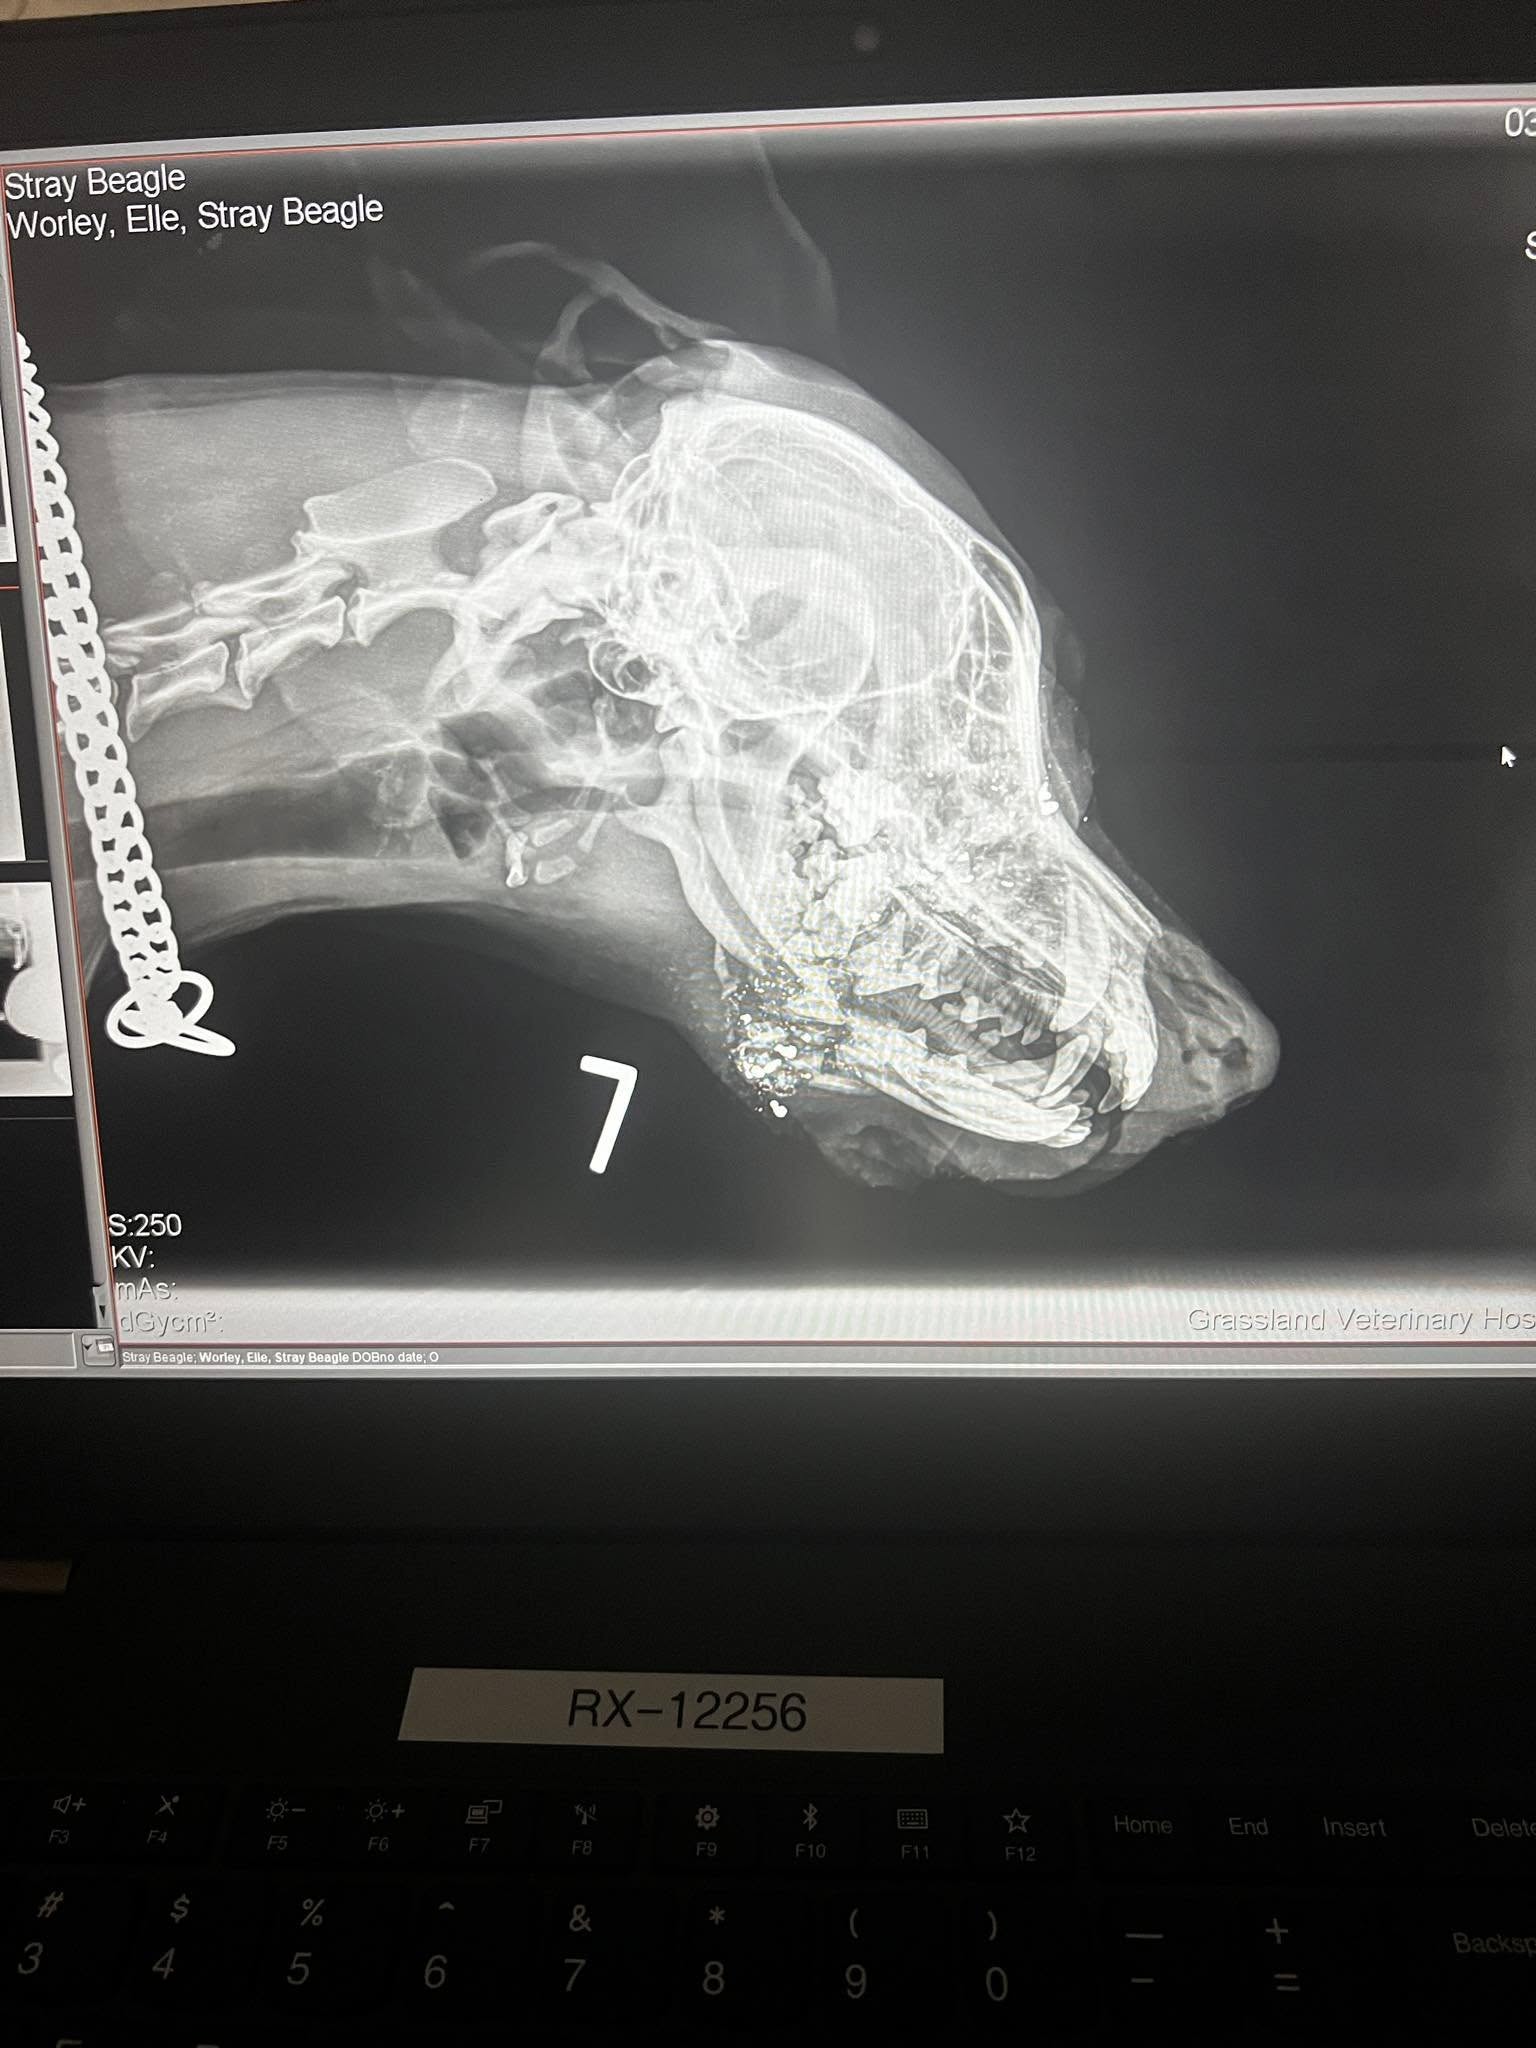

The Nebraska veterinarian revealed that Juni had been shot twice in the jaw. The bullets had narrowly missed her brain by mere inches. Elle was stunned by the cruelty of the act and knew Juni needed immediate medical attention.

Along with pain relief, Juni required emergency surgery to repair her jaw.